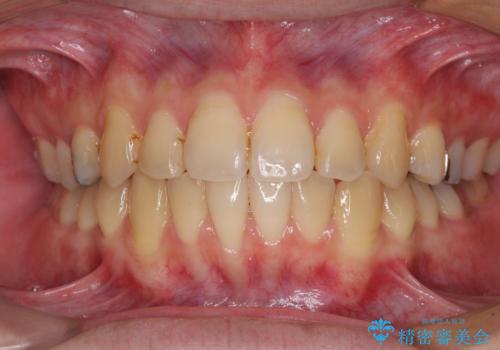

前歯のクロスバイトをインビザラインで矯正治療

- 前歯のデコボコとクロスバイトを気にして来院された患者様です。

前歯を早く整えたいとの希望があったので、ワイヤー矯正にて短期間でクロスバイトを解消し、その後インビザラインにて整えることとしました。

インビザラインによる前歯のクロスバイト改善におけるリスクとして、前歯歯髄充血・歯髄壊死が挙げられます。

ワイヤー矯正を併用する目的として、短期間でデコボコやクロスバイトを改善する他に、歯髄充血リスクを低減させるというものがあります。